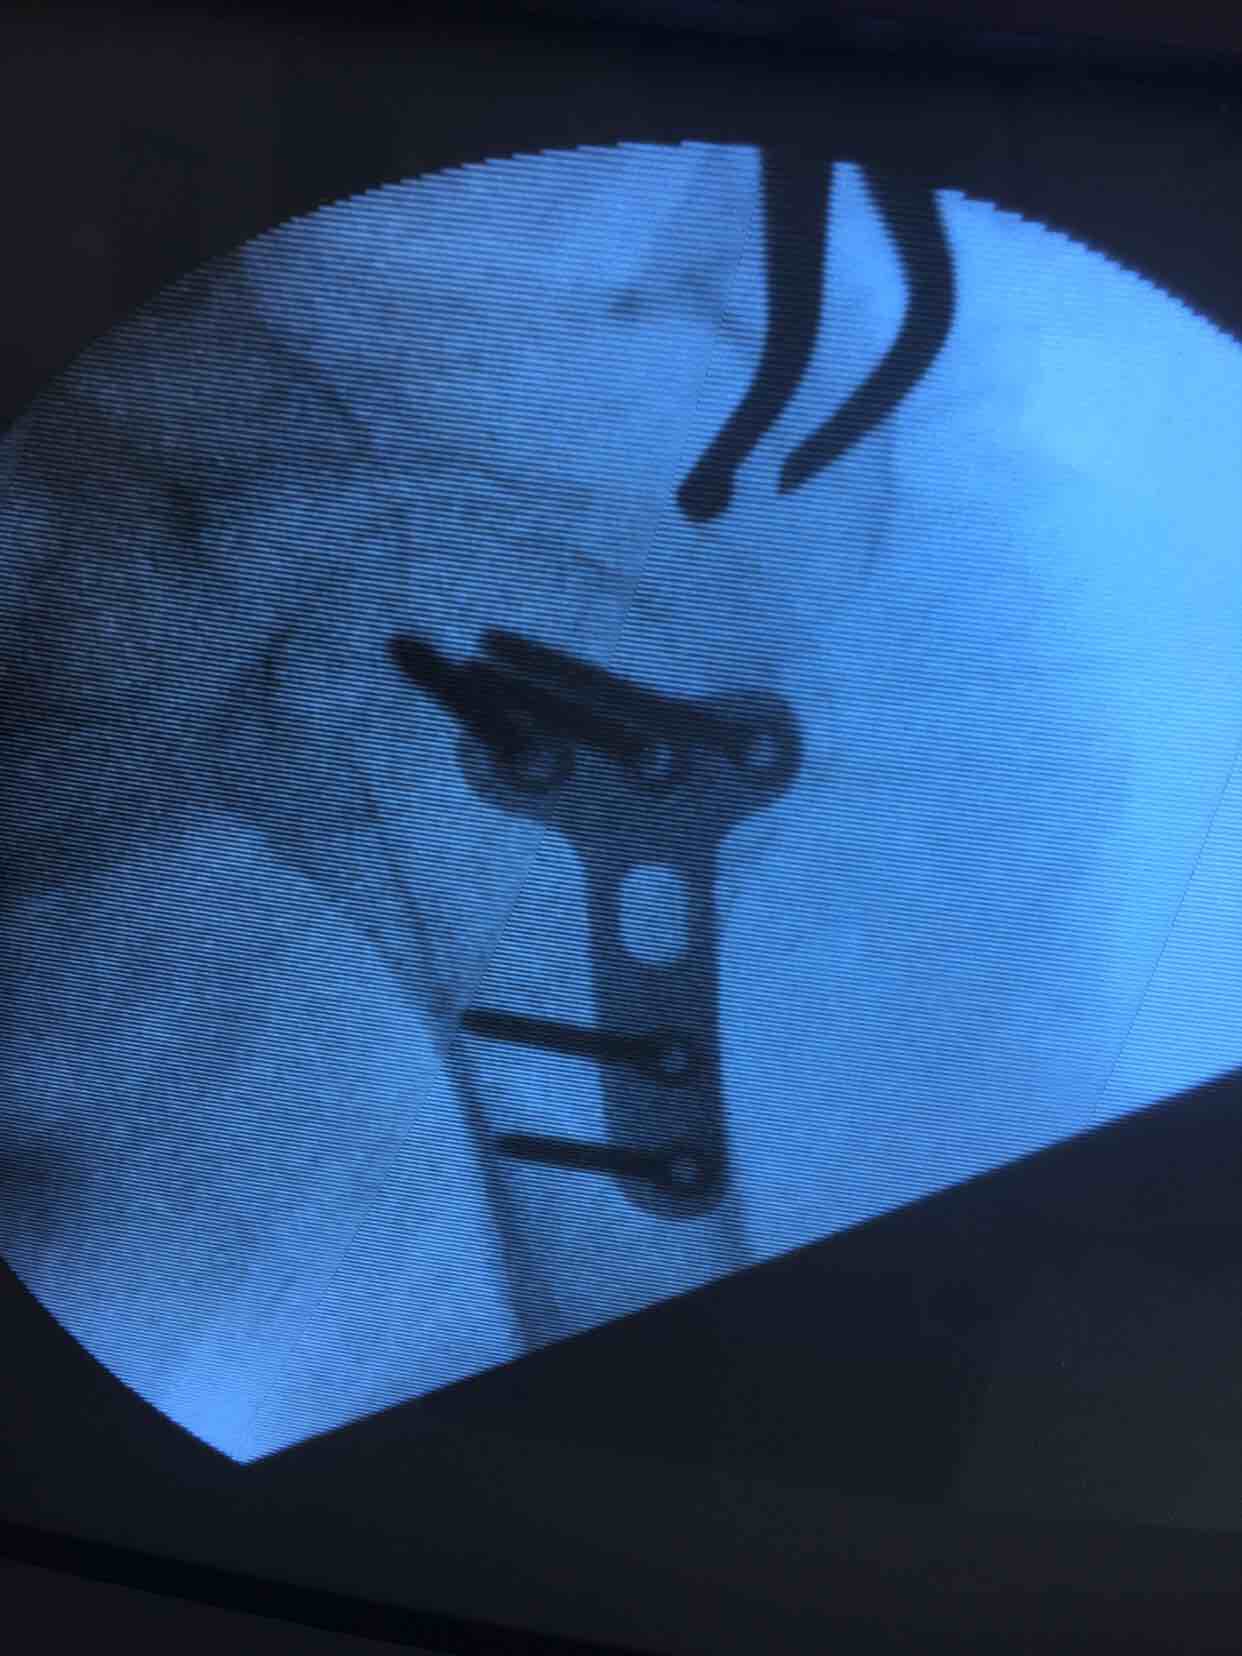

肩关节脱位并大结节骨折(切复内固定)

摔伤后右肩部肿痛,活动受限1天入院。既往患有冠心病数年,无特殊不良嗜好。

生命体征平稳,心肺腹未见异常。右肩部肿胀明显,局部皮色青紫淤瘢,皮温基本正常,搭肩试验阳性,关节盂空虚,肩关节活动受限,远端血运感觉正常。

诊断肩关节脱位并大结节骨折在臂丛麻醉下行切复内固定术,术后外展架固定,抗炎,消肿等处理。